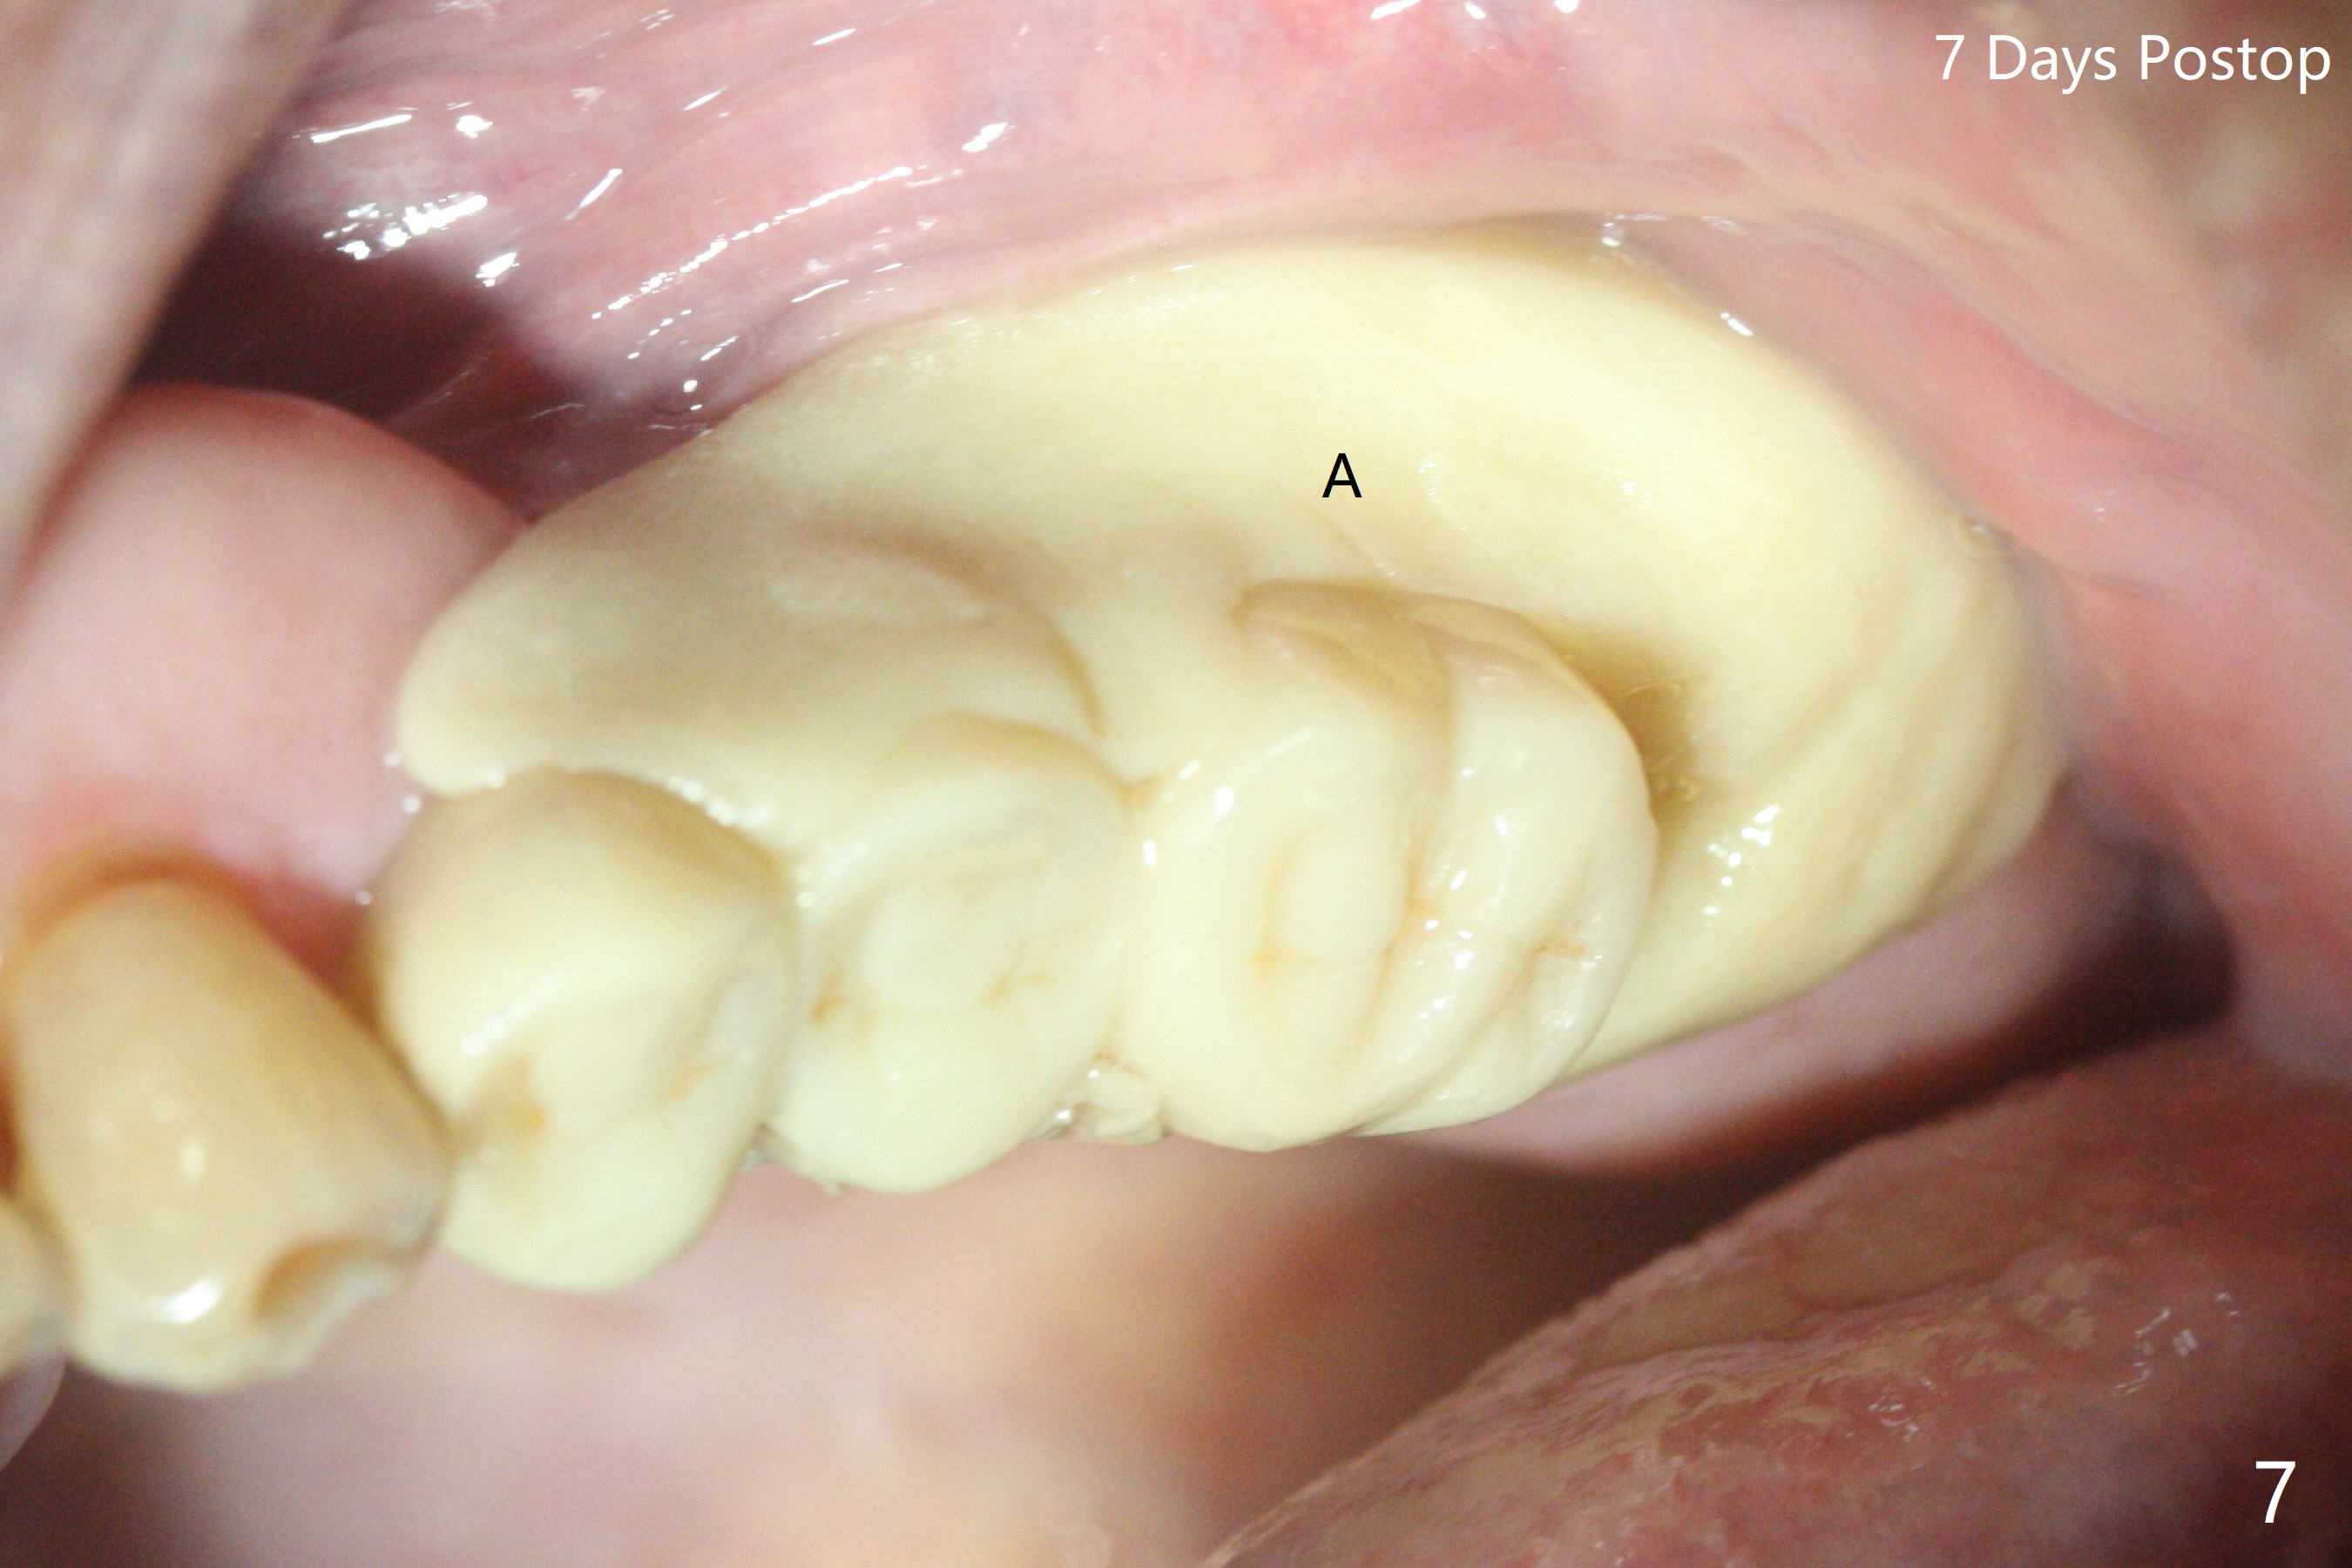

86岁男左上7折裂(图一),要求拔除,经过讨论(7拔除后,4-6悬臂桥可能断裂,对植体产生创伤,图二(左下7存在)),同意植骨。拔牙时发现中隔特别粗大(图三,五:S),三个牙槽窝根尖好像在中隔下面相互交通,擤鼻涕却没有气泡,仿佛与上颌窦没有相通。艰难清创后,放置Vanilla骨粉(图三),腭侧根特别容易填满,而颊侧根填入许多骨粉,术后CT远中颊侧骨粉尤其多(图四),上颌窦粘膜增厚(原来有季节性过敏)。术前根尖片显示远中颊侧根尖周围阴影很长(图五,六(虚线))。第二天早上鼻出血(仅有一次),今后牙槽窝明显比牙根长,清创控制深度,先放置胶原塞或PRF膜,后放骨粉。病人已经购买水牙线。术后7天树脂敷料稳定,局部卫生好(图七),骨粉好像进入上颌窦后部(图八)。术后1.5个月树脂敷料仍在原位,很容易撤除,牙槽窝愈合(图九),骨粉好像没有丢失(图十)。